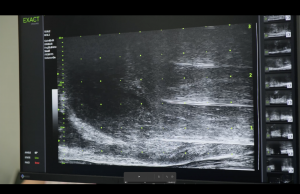

პროსტატის მიკროექოსკოპია წარმოადგენს დიაგნოსტიკურ მწვერვალს პროსტატის დაავადებათა დიაგნოსტიკაში, რომელიც ხელმისაწვდომია რეგიონში მხოლოდ ჩვენს კლინიკა ქარაზანაშვილის რობოტულ ცენტრში. მას არ გააჩნია ანალოგი მეზობელ ქვეყნებში (თურქეთი, რუსეთი, აზერბაიჯანი, სომხეთი), ხოლო ევროპასა და ჩრდილოეთ ამერიკაში ხელმისაწვდომია მხოლოდ წამყვან კლინიკებში. მუშაობის პრინციპი დაფუძვნებულია ულტრაბგერის მაღალ სიხშირეზე, რომელიც იძლევა 300%-ით გაუმჯობესებული გამოსახულებას ტრადიციულ ულტრაბგერასთან შედარებით. გამოსახულების „ცოცხალ“ რეჟიმში ვიზუალიზაციისა, კიბოზე საეჭვო უბნების გამოვლენისა და თარგეტული ტრანსპერინეული ან ტრანსრექტალური ბიოფსიისთვის, მიკროექოსკოპიას არ გააჩნია მსოფლიოში ანალოგი.

პროსტატის ტრანსპერინეული და ტრანსრექტალური თარგეტული ბიოფსია მიეკკუთვნება მცირე პროცედურებს უროლოგიაში. პროცედურის დროს სპეციალური გადამწოდი თავსდება სწორ ნაწლავში, რომელიც ახდენს პროსტატის ვიზუალიზაციას, ხდება სიმსივნეზე საეჭვო უბნების გამოვლენა და მათი ბიოფსია. ორგანოდან ქსოვილის მცირე ფრაგმენტის აღება ხორციელდება სპეციალური ნემსითა და საბიოფსიო მოწყობილობით ტრანსრექტალურად ან ტრანსპერინეულად. პროცედურა არის ხანმოკლე (5-7წთ) და არის უმტკივნეულო.

პროსტატის ბიოფსია მიკროექოსკოპული კონტროლით ეფექტურად ავლენს პროსტატის კიბოზე საეჭვო უბნებს და 100% დამიზნებით ახორციელებს ქსოვილის აღებას საჭირო უბნებიდან. მისი ეფექტურობა დამტკიცებულია არაერთი სამეცნიერო კვლევით. თუმცა მხოლოდ აქ არ მთავრდება მისი ეფექტურობა. შესაძლებელია პროსტატის მაგნიტურ-რეზონანსული ტომოგრაფიის შერწყმა ( FUSION) პროსტატის მიკროექოსკოპიის ცოცხალ გამოსახულებასთან, რომლის ეფექტურობა თითქმის 100%-ა. ეს მეთოდი წარმოადგენს პროსტატის ბიოფსიის უმაღლეს მიღწევას, რომელიც არის უახლესი სიტყვა თანამედროვე მედიცინაში.